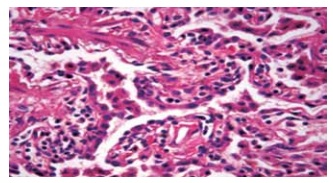

Legenda: Macrófagos com ferro.

O diagnóstico de DIP (pneumonia intersticial descamativa) foi feito correspondendo à clínica de pulmão do tabaco. O parênquima pulmonar demonstra presença de macrófagos intra-alveolares, multinucleados e com pigmento granular castanho contendo ferro, que é demonstrado pela técnica

Legenda: Macrófagos com ferro. (Laboratório de Anatomia Patológica do Centro Universitário FMABC. Imagem usada com autorização)